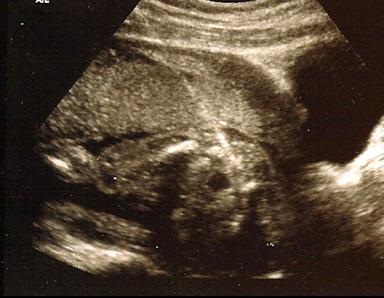

Amniocentesis was the first method developed for prenatal diagnosis – dating back to the late 1960s and early 1970s. It is usually performed between 15 and 20 weeks from the beginning of the last menstrual period. Under ultrasound guidance a thin needle is inserted through the woman's abdominal wall and into the uterus and amniotic cavity. The procedure feels like having blood drawn. Approximately one ounce of fluid is withdrawn and sent to the laboratory for analysis. In experienced hands, genetic amniocentesis is a very safe test. A significant limitation of amniocentesis, however, is that reassurance or diagnosis of problems does not occur until the mid to late second trimester.

Chorionic villus sampling, or CVS, is the first-trimester procedure for prenatal diagnosis of fetal chromosomal and genetic disorders, usually performed 11 to 13 weeks from the beginning of the last menstrual period although in some instances it can be used much later in pregnancy. The procedure is done one of two ways. In singleton pregnancies, most of the time (about 70% of the time for us) we place the patient in stirrups, and a speculum is inserted just as for a Pap smear. A small plastic catheter (similar to a straw) is passed painlessly through the cervix and maneuvered under ultrasound guidance into the placental tissue. A syringe is then attached to the end of the catheter, and a very small amount of placental tissue is aspirated. In some cases (about 30% of the time for singletons), depending upon the position of the placenta, a needle may be inserted transabdominally, like an amniocentesis, and maneuvered into the placenta (not the fluid). Most American women given the choice between a “Pap smear” like experience or a needle, prefer the “Pap Smear.” In experienced operators, however, do as many as 90% of cases abdominally, because they do not have the experience to perform the vaginal approach.